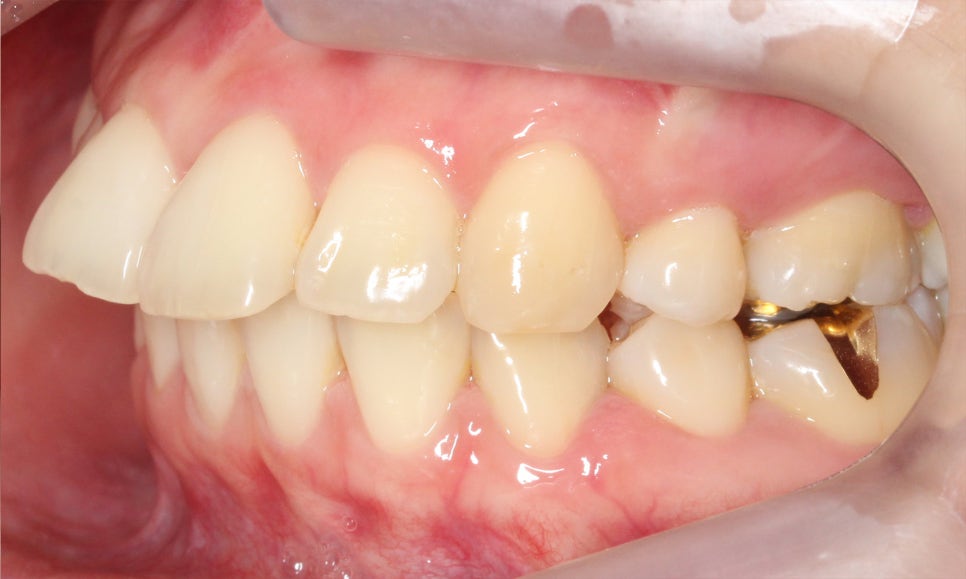

좌우 교합 평면의 모습을 보면

협측 사진에서 중절치의 돌출감이

심한 모습을 볼 수 있는데요,

구치부의 교합 상태를 보니

윗니가 과도하게 앞으로

튀어나와 있는 2급 부정교합이

의심되는 모습입니다.